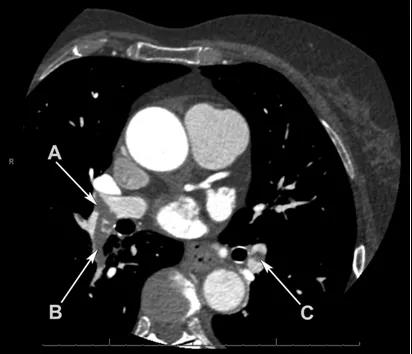

一名73岁的女性因不典型性胸痛来就诊,患者无心血管疾病病史,无其余特殊相关体征和症状。作为常规检查,在胸痛诊疗中心给患者做了冠脉CTA。动脉相的冠脉CTA可见右肺动脉主干远端,右下叶肺动脉,左下叶肺动脉有弥漫性的低密度灶。冠脉无异常发现。尽管该检查并非肺动脉栓塞的首选影像手段,但影像学结果能够将病人诊断为弥漫性双侧肺动脉栓塞。因此最终诊断为弥漫性双侧肺动脉栓塞。

动脉相的冠脉CTA可见右肺动脉主干远端,右下叶肺动脉,左下叶肺动脉有弥漫性的低密度灶